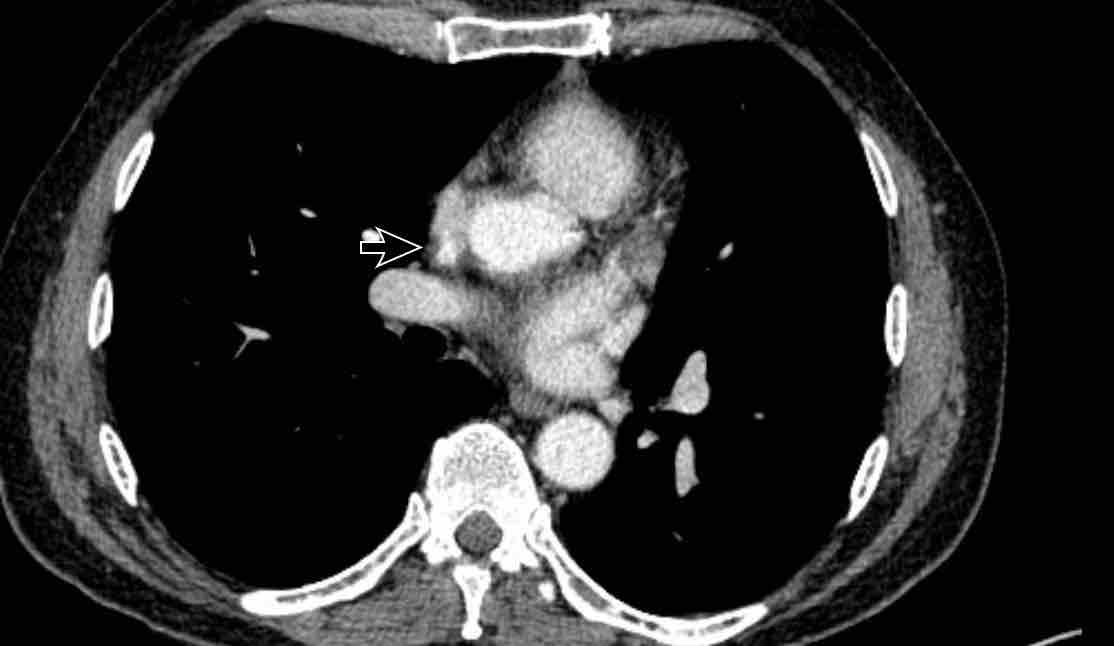

Hình ảnh

Bệnh nhân này được lên kế hoạch cắt thùy trên phải do ung thư phổi và bất thường mạch máu này ban đầu đã bị bỏ sót trên hình ảnh CT.

Những hệ quả trong phẫu thuật của bất thường như vậy nhấn mạnh tầm quan trọng của việc không bỏ sót các biến thể này.

Cuộn qua các hình ảnh.

PAPVR bên trái phát hiện tình cờ với dẫn lưu trên tim của máu từ thùy trên trái vào tĩnh mạch tay đầu trái (các mũi tên).